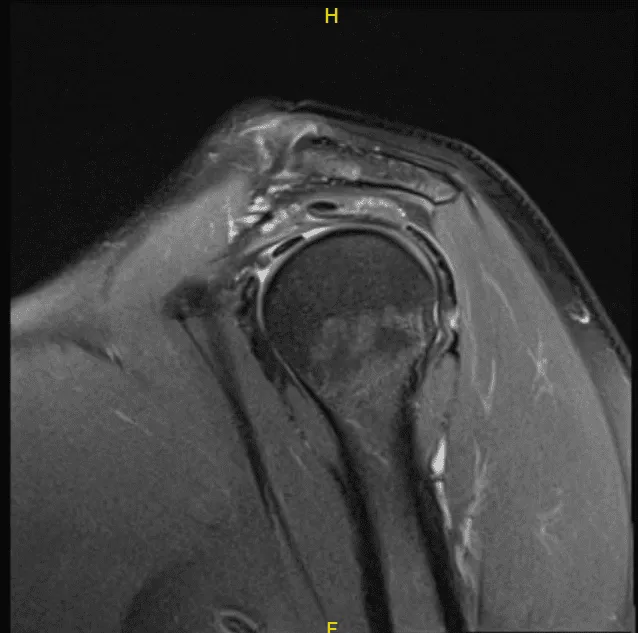

The patient presented an MRI result that showed multifocal rotator cuff tendinosis with a delaminating high-grade partial-thickness intrasubstance insertional tear at the confluence of the supraspinatus and infraspinatus tendons.

Mild tendinosis of the intra-articular portion of the biceps tendon. Mild degeneration with fraying/tearing at the base of the superior labrum. Very mild acromioclavicular joint arthrosis. Mild subacromial-subdeltoid bursitis.

MRI-3T left shoulder non-contrast